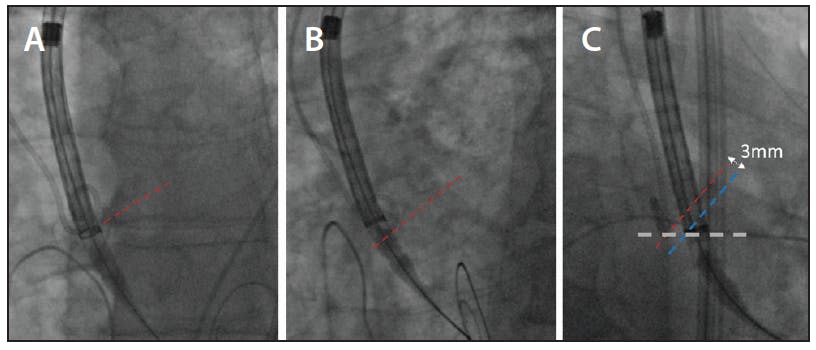

Furthermore, as the COV puts the lowest point of the NCC lateral to the valve, rather than behind the valve (as in the three-cusp view and modifications) visualisation of its position is further simplified (Figure 2). With the pigtail firmly at the base of this cusp, the device can be easily adjusted relative to the base of the pigtail. We have also been confident that when the valve is below the NCC in the COV it will be below all three cusps in almost all cases. As Medtronic now recommends, we aim to place the valve at a target implantation depth of 3 mm, with a range of 1 to 5 mm; shallower implantations may lead to pop-outs during postdilation, whereas deeper implants increase the pacemaker rates. This cusp overlap technique has allowed us to greatly simplify deployment (Figure 2).

Figure 2. Valve ring level with the annulus (red line) in three-cusp view but valve not in plane (valve ring oval shape) (A). Following LAO angulation, valve in plane but now looks high relative to the pigtail and a line joining NCC and LCC (B). Valve at optimal height (blue line) 3 mm below the annular plane (red line) (C).